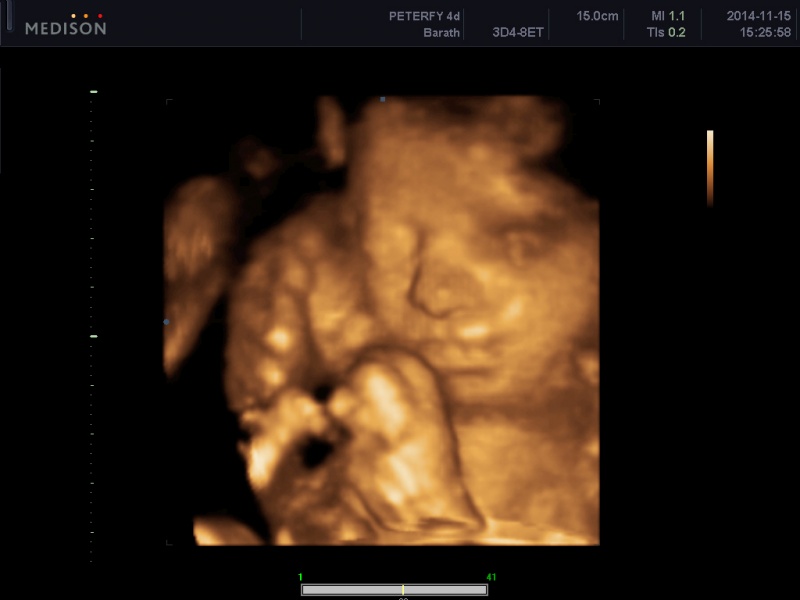

Haany, ha biztosra akarsz menni, akkor várd meg a nemvár utáni 1 hetet, akkor már eléggé valószínű, de h ha negatív esetleg, akkor se ess kétségbe. van hogy lassaban termeli a szervezet a HCG-t vagy a meágyazódás kicsit késöbb volt, menj el dokihoz esetleg, ha nem jön meg és megvannka a tünetek is még, én késé után 1 héttel voltam és a nődoki azt mondta, hogy lát valamit, a méhfalam is megvan duzzadva, de 2 hét múlva menjek el újra, de addig vérvétel( a vérből hamarabb kimutatják a HCG-t ) 2 hét múlva visszamentem, és már 7 hetes volt a kis ficánkám és dobogott a pici szive, oriási 13mm-es hosszal :) most 29 hkm vagyok és 1 gyönyörű picilány fészkelődik odabent :)